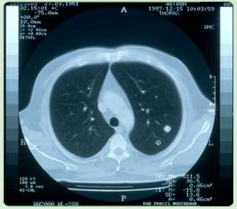

Lungenmetastasen vor RTH - Lungenmetastasen nach RTH

Bronchial - CA

diffuse Lungenmetastasierung eines mucinösen Adeno - CA - s unklaren Ursprungs (CUP-Syndrom) ED 1/97 2 malige Regionale Chemotherapie in Kombination mit 12 Behandlungen regionaler Tiefenhyperthermie (3 x / Woche) führten zur Vollremission; aus

Mastall H. Zeit- und situatiosgerechte Einsatzmodelle für komplementäre Verfahren während

konventionell-onkologischer Therapien.

32. Medizinische Woche Baden-Baden 1998; 02.XI